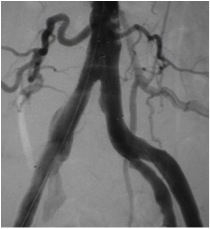

A cirurgia convencional (aberta) é feita através da confecção de “pontes” que desviam o fluxo sanguíneo na área obstruída.